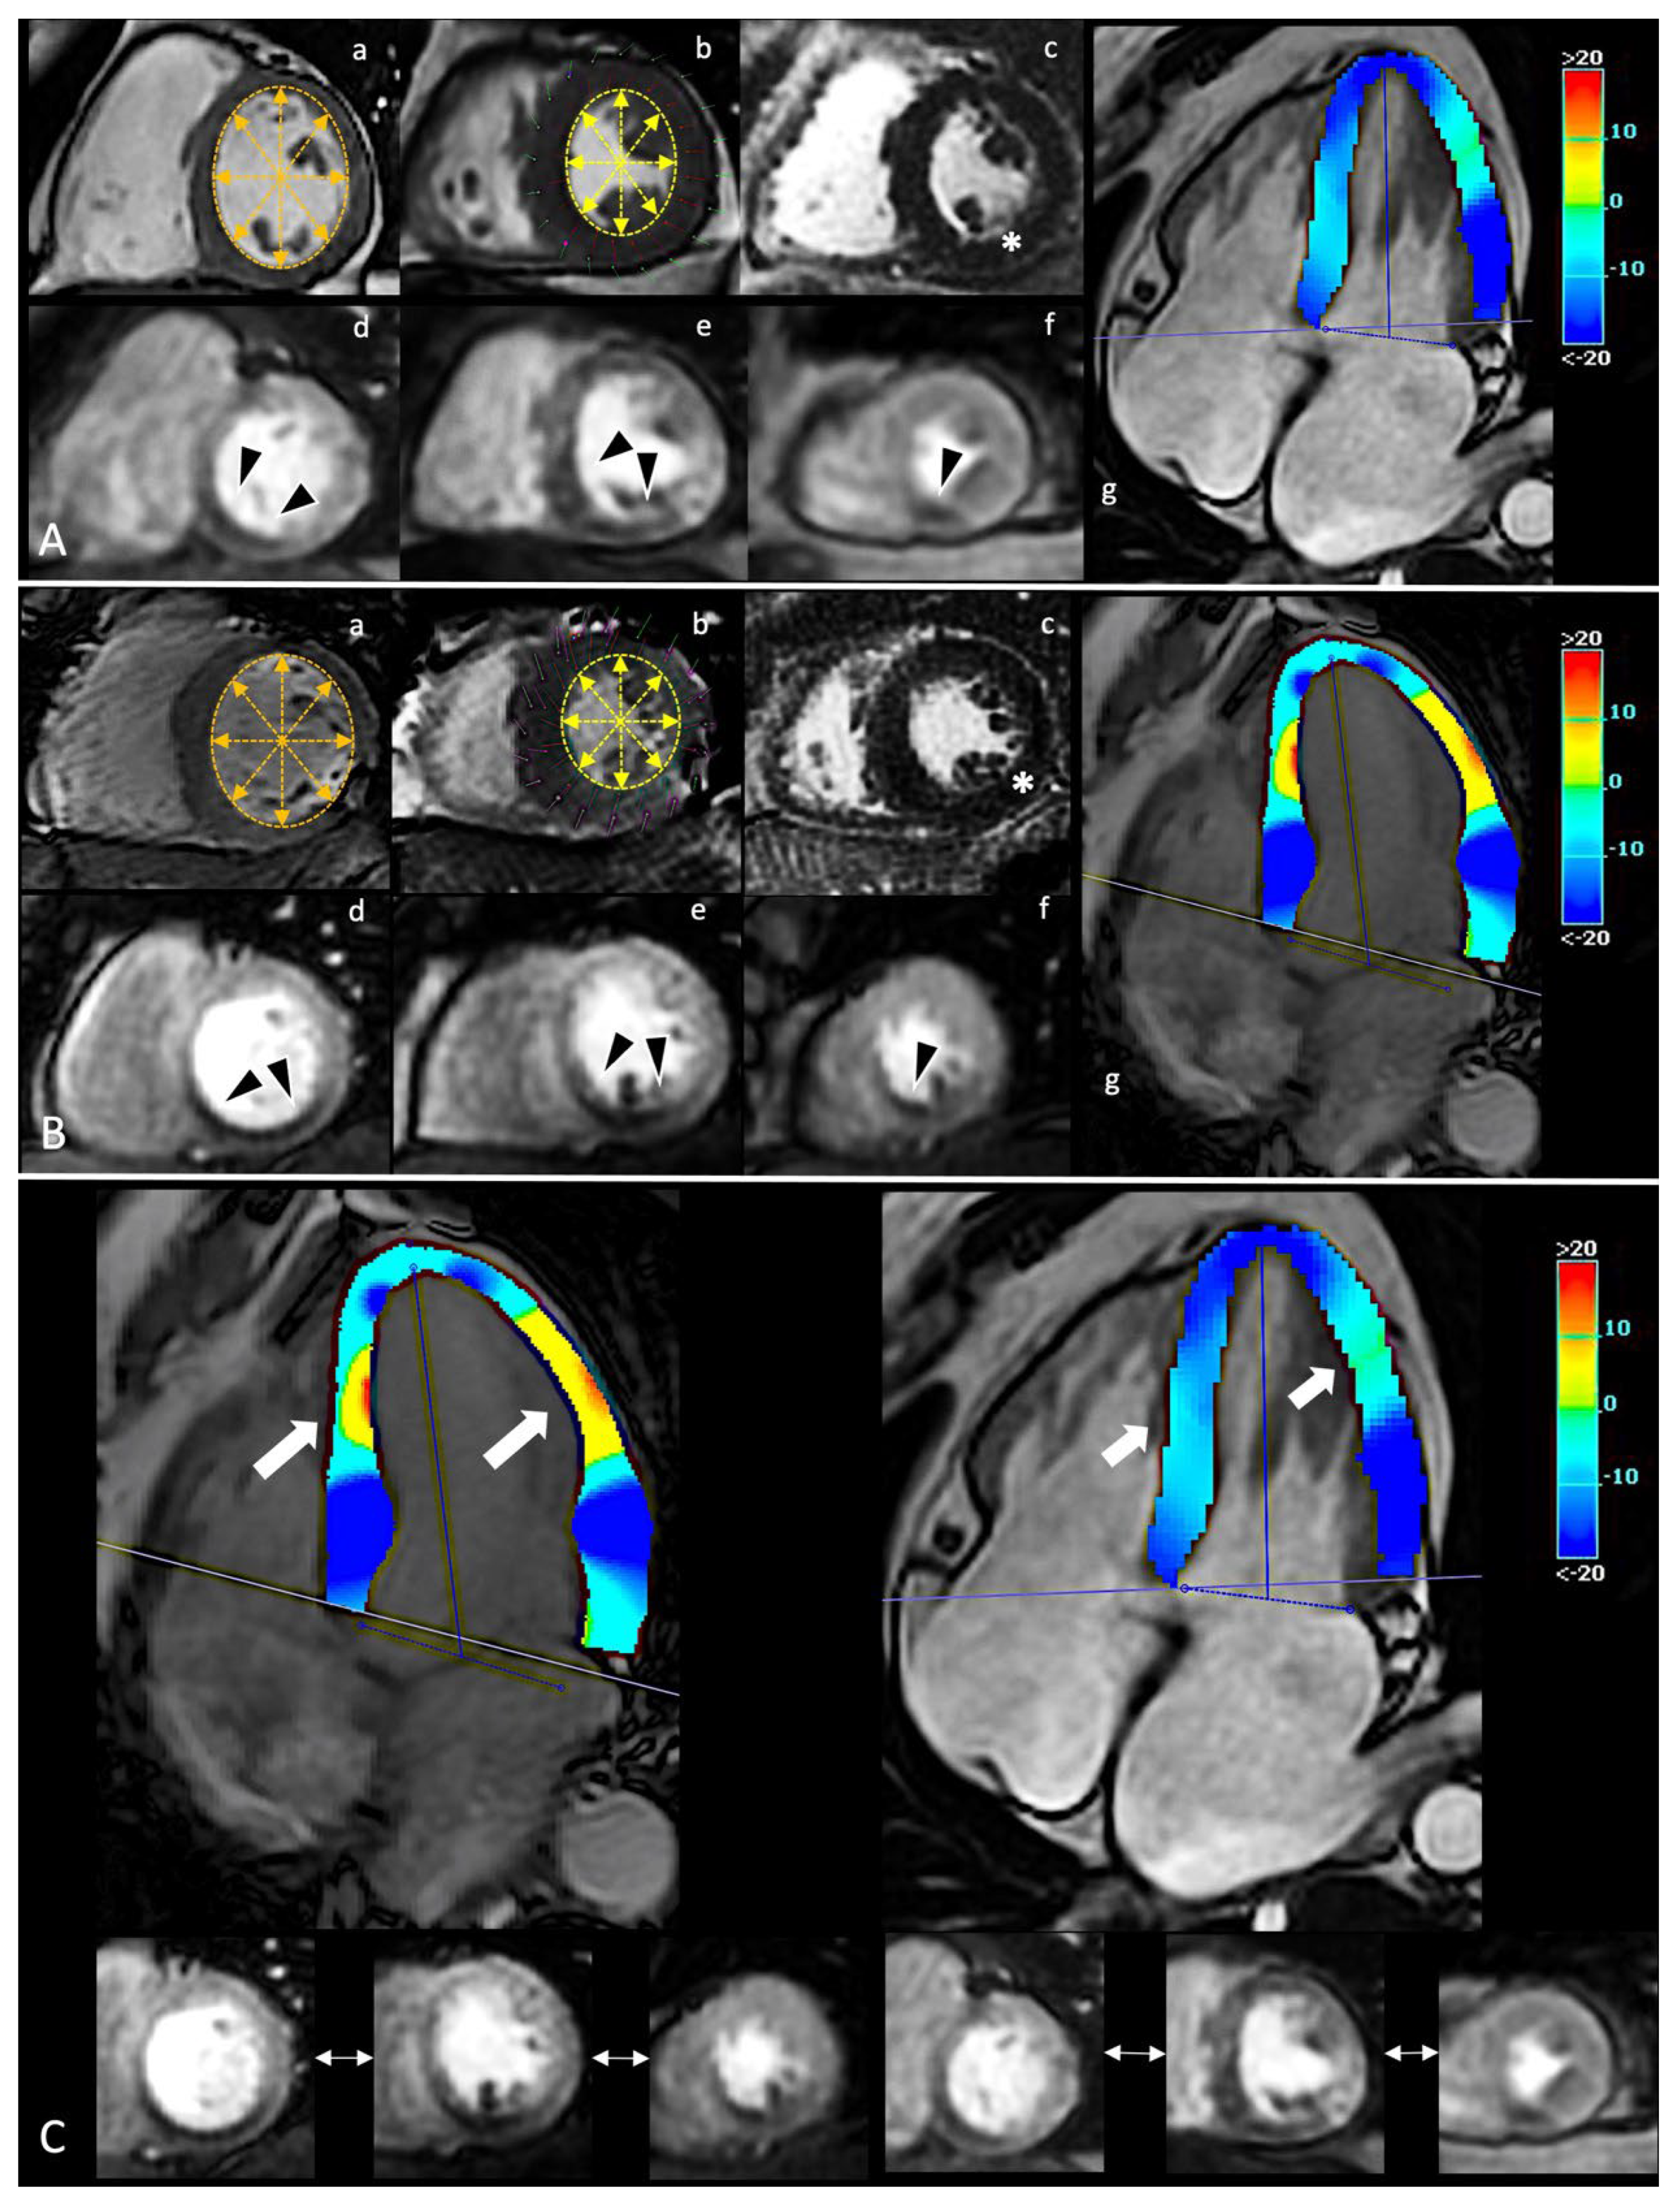

Figure 1. In panel (A,B), spCMR findings of two CCS patients. In (a,b), a single frame from SA cine sequence in diastolic and systolic phase, respectively; changes of inner double-arrows lines length highlight preserved systolic contraction. In (c), evidence of no enhancement in LGE sequences (white asterisk). In (d–f), a single frame from first-pass perfusion during adenosine infusion with evidence of similar ischemic burden involved inferior segments from the base to the apex (black arrowheads). In (g), a single systolic frame from HLA cine sequence with superimposed colorimetric map of GLS. On the right, the legend of colorimetric map with correlation between values and colors. In panel (C), the comparison between the different GLS. Despite a similar ischemic burden, the two patients report different GLS abnormalities (white thick arrows), suggesting a different impact of ischemia on global deformability. GLS acts as accurate index of early global impairment beyond the focal injury. spCMR: stress perfusion cardiac magnetic resonance; CCS: chronic coronary syndrome; SA: short-axis; LGE: late gadolinium enhancement; HLA: horizontal long-axis; GLS: global longitudinal strain.

However, the GLS only resulted significantly different for CCS patients categorized for the presence of ischemia (−14 ± 2% vs. −17 ± 1%, p-value 0.0001) (Figure 1).

Ischemic burden correlates with GLS (r: 0.699, p-value: 0.0001). Moreover, when GLS was categorized for reduced or preserved values, ischemic burden was predictive of GLS impairment (OR: 1.33, 95%CI: 1.08–1.64; p-value 0.008).

• CMR-related strain confirms its ability to stage myocardial damage, which could translate into a critical ability to predict disease progression [99,100]. Among CCS patients with ischemia and no other conventional imaging predictor, GLS resulted highly impaired with a good correlation with the ischemic burden. This correlation proves GLS (an indicator of global function) as effective in describing the real impact of ischemia on cardiac function beyond the localized distribution of ischemic damage [101].